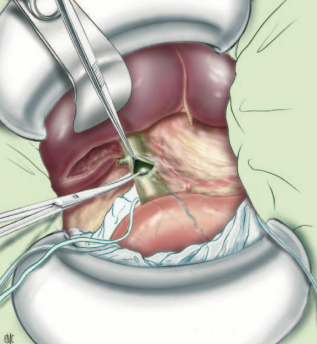

Khâu chỗ mở OMC: Có 3 phương án:

- Khâu kín thì đầu không dẫn lưu: Là ưu việt nhất, nhưng đòi hỏi kiểm tra không tổn thương phù nề cơ Oddi, đảm bảo sạch sỏi, thành ống mật không viêm mủn nát, không có viêm mủ đường mật;

- Khâu đường mật kèm dẫn lưu Kehr: Kinh điển được dùng cho gần như tất cả BN. Lợi điểm: Chụp đường mật sau mổ kiểm tra, cũng như xử trí tiếp nếu như còn sỏi;

- Khâu đường mật kèm dẫn lưu qua ống túi mật.

Hình. Khâu lại chỗ mở OMC

A – Không dẫn lưu. B – Dẫn lưu Kehr. C – Dẫn lưu qua ống mật